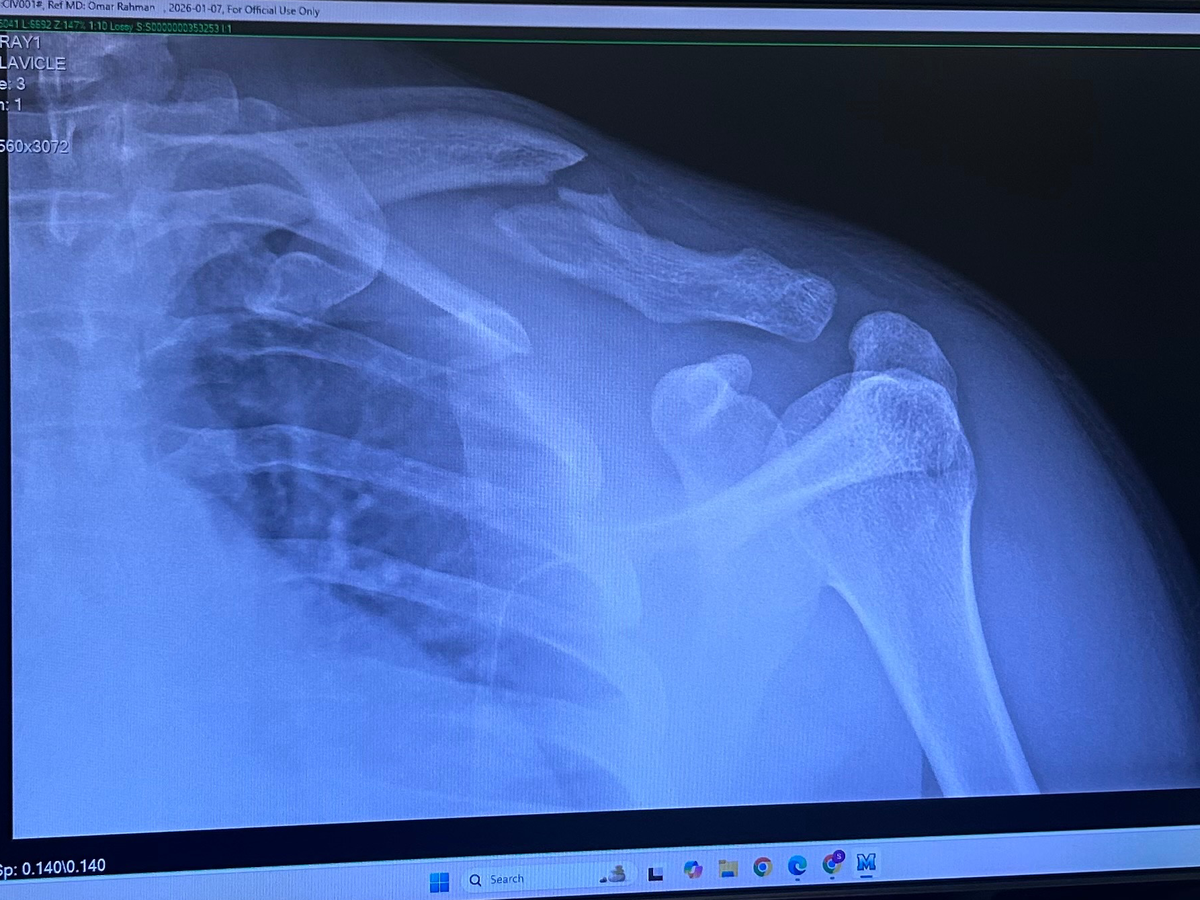

On December 29th, my life took an unexpected turn when I was hit by a car while riding a Lime scooter. The accident left me with a broken clavicle and significant bruising on my hips and legs. As a result, I need surgery on my collar bone and have been unable to attend work. Not having health insurance has made this situation even more challenging, as the medical bills and daily living expenses are quickly adding up.